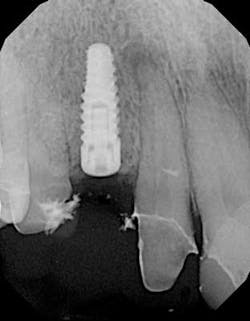

Using the surgical index as a reference, a 3.8 x 12 tapered implant was placed in a prosthetically driven manner. During placement, a 3 x 3 mm fenestration of the buccal plate occurred at the apical extent of the implant. Using a combination of enamel matrix derivate mixed with cortico-cancellous allograft placed in a bone syringe, the area of fenestration was grafted. Although the implant achieved 35 Ncm of stability, a cover screw was placed and primary coverage was achieved. A conventional two-stage procedure was selected because of the regenerative demands of this particular case. The area was then temporized with a newly fabricated lab-generated acrylic bridge with careful attention to pontic site development.

Immediately post-insertion, a periapical radiolucency was detected on the post-insertion radiograph on tooth No. 7 and the patient was immediately sent for root canal therapy. Four months was allowed for implant integration. At the time of Stage II, a noninvasive punch tissue technique was employed and a 3 mm healing abutment was placed. At the time of impression, an open tray technique was used and a custom abutment was selected. Because of the patient’s canine guidance occlusion, a porcelain-fused-to-metal crown was selected along with all-ceramic crowns on teeth Nos. 5 and 7.